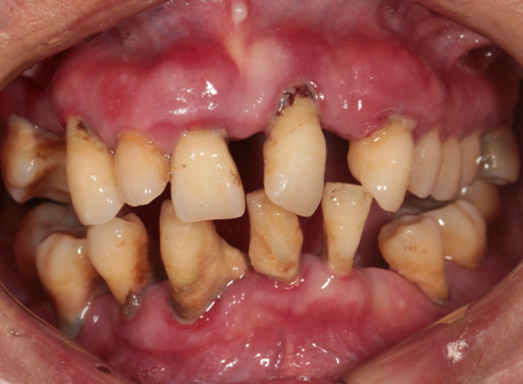

Intraoral Examination(A zone=Right upper jaw、B zone=Left upper jaw、C zone=Left lower jaw、D zone=Right lower jaw)

Poor oral hygiene, accumulation of calculus, three-degree loosening of the entire mouth

Periodontitis causes severe absorption of the upper and lower jaws

A zone A4-A6、B zone B2、C zone C2-C4、D zone D2-D3 lost

A zone A1-A3、A7、B zone B1、B5-B7、C zone C1、C5-C7、D zone D1、D4-D8 all with III°loosen

Photos of preliminary oral diagnosis